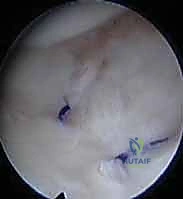

* الارتباط بالناتئ الإبري: ترتبط العديد من أربطة الـ TFCC مباشرة بالناتئ الإبري للزند (Ulnar Styloid). لذلك، فإن أي كسر في قاعدة الناتئ الإبري غالبًا ما يصاحبه تمزق في هذا المركب الغضروفي، مما يؤدي إلى عدم استقرار شديد في المعصم يستوجب تدخلًا جراحيًا دقيقًا، وهو ما يبرع فيه الأستاذ الدكتور محمد هطيف باستخدام تقنيات المناظير (Arthroscopy).

3. الرنين المغناطيسي (MRI): يُطلب عند الاشتباه القوي بوجود تمزقات في الأربطة والمركب الغضروفي (TFCC) التي لا تظهر في الأشعة السينية.